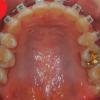

[치아교정후기27] 교정만의 오라픽스 치아교정후기 - 위 아래 철사 감았어요~

[치아교정후기27] 교정만의 오라픽스 치아교정후기 - 위 아래 철사 감았어요~ 안녕하세...